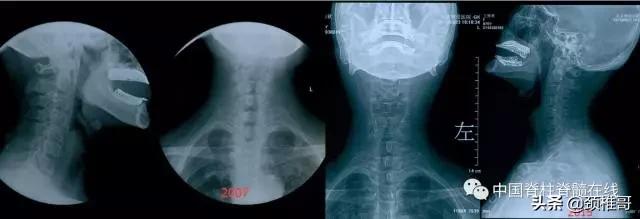

神经根型颈椎病是在肌肉、韧带、椎间盘、骨和关节都已经发生退变,颈椎动态不稳和静态不稳同时存在,代偿性的增生、钙化、韧带肥厚等综合作用下,神经根管狭窄,神经根受压所导致的一种类型颈椎病。我们可以应用中西医药物、适度牵引、理疗等临床治疗方法缓解症状;同时应用主动抗阻运动疗法进行康复训练,增强患者的颈椎周围动态和静态稳定性,筑牢颈椎健康金字塔的根基。如果患者长期坚持康复训练,颈椎稳定了,不需要再通过代偿性增生稳定了,原有的骨质增生就会得到遏制,甚至部分增生的骨质可以被吸收、重塑。这是一位71岁的老人,交感型加神经根型的混合型颈椎病。通过长期的康复训练之后,部分增生的骨质吸收了,颈椎也稳定了,交感神经和神经根的症状都消失了,获得了较好的长期疗效。

长期的康复训练后部分增生的骨刺可以吸收